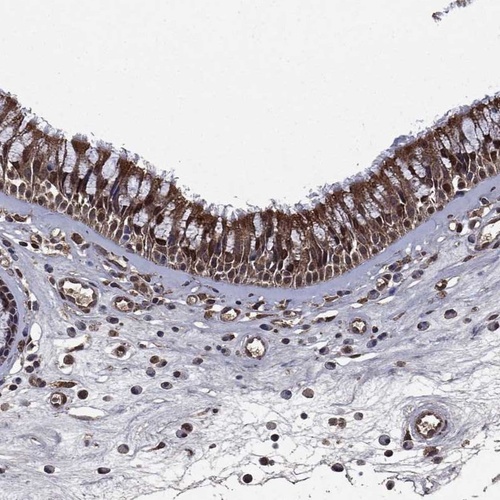

Immunohistochemical staining of human nasopharynx shows strong nuclear and cytoplasmic positivity in respiratory epithelial cells.